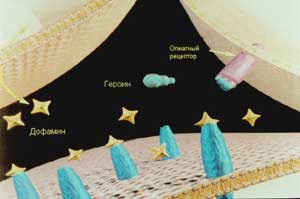

Рассмотрим это на примере, который сейчас стал очень злободневным: хирургическое лечение обусловленного потреблением наркотиков обсессивно-компульсивного синдрома. Одним из страшных свойств наркотика является привыкание к нему, привыкание настолько, что наркоман становится зависим от него, не может без него жить. Есть два типа зависимости: физическая и психологическая. Первый тип зависимости обусловлен встраиванием героина в механизм потребления энергии клеткой мозга. Клетка привыкает питаться по облегченному (но не эффективному) варианту и не хочет возвращаться к старому и эффективному. Поэтому при прекращении приема наркотика происходит «ломка» - абстиненция, которая крайне мучительна и может кончиться даже смертью наркомана. Однако современная медицина научилась относительно легко и безболезненно справляться с этим, существуют различные, очень эффективные способы устранения физической зависимости, которые с успехом применяются во многих клиниках. Итак, наркоман «отмыт». Его организм более не нуждается в наркотиках. Но он помнит о том великолепном ощущении, которое он испытывал при их употреблении, и всеми фибрами своей души мечтает еще раз его испытать. Это не блажь, это тяжелое психическое заболевание: обсессивно-компульсивный синдром - и противиться этому влечению невозможно. На него не действуют разумные доводы. К сожалению, до сих пор эффективность лечения психологической зависимости от наркотика чрезвычайно низка и составляет от 3 до 8 процентов. Учитывая то, что средний срок жизни героинового наркомана четыре года, можно сказать, что больной обречен. В этом смысле героин можно сравнить с злокачественной опухолью, и, как правило, можно говорить не об излечении, а о сроке выживания, отсрочке страшного конца.

В нашей клинике используется хирургический метод лечения героиново обусловленного обсессивно-компульсивного синдрома. Теоретическое объяснение и самого синдрома, и механизма действия предложенного метода лечения еще не может считаться полностью завершенным, поэтому ниже будет приведена одна из концепций, которую мы считаем наиболее вероятной. Естественно, что в данной статье, рассчитанной на массового читателя, она будет приведена в упрощенной форме, за что приношу свои извинения специалистам.